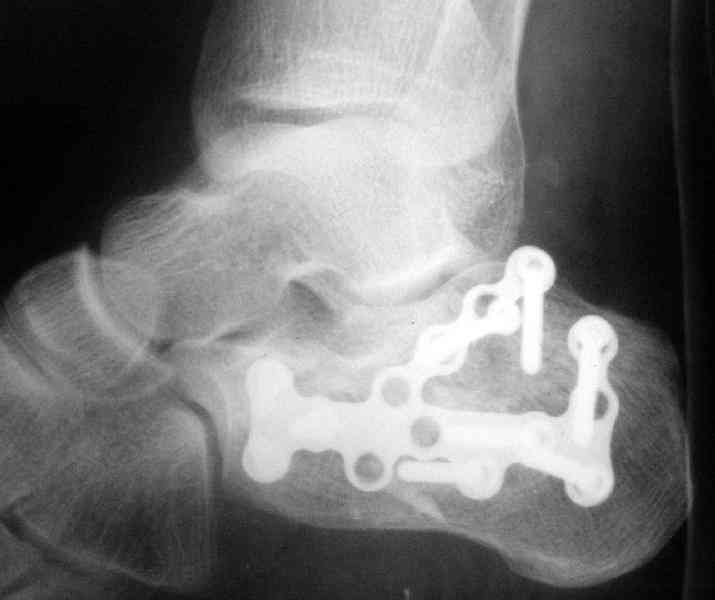

Пяточной пластиной

Открытый и закрытый способы лечения.